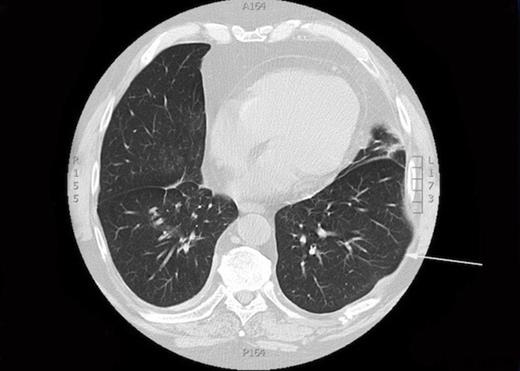

A CXR scan was performed which illustrated atelectasis at his left lung base. A subsequent CT demonstrated intercostal lung herniation alongside fractured sixth, seventh and eighth ribs, arising as a result of chest wall deformity (figure 1). Images were subsequently reconstructed by a clinical radiologist to fully demonstrate the skeletal pathology. (figure 2)